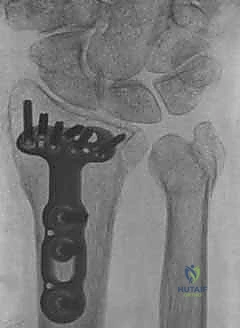

ثانياً: العلاج الجراحي (Surgical Intervention)

متى يقرر الدكتور هطيف ضرورة التدخل الجراحي؟

1. عدم الاستقرار (Instability): إذا كان المفصل الزندي الكعبري البعيد (DRUJ) غير مستقر بعد تثبيت كسر الكعبرة.

2. الانزياح (Displacement): إذا كان الكسر في قاعدة الناتئ الإبري منزاحًا بأكثر من 2 ملم.

3. الكسور المفصلية: أي كسر يخل بتطابق السطح المفصلي لرأس الزند.

4. الكسور المفتتة: في الجزء الكردوسي التي تؤدي إلى قصر عظم الزند.

5. الكسور المفتوحة (Open Fractures): حيث يبرز العظم من الجلد، وتتطلب جراحة طارئة لتنظيف الجرح وتثبيت الكسر لمنع العدوى.

التخطيط الجراحي لكسور الزند

1. التخطيط ما قبل الجراحة (Pre-operative Planning)

يقوم الدكتور هطيف بدراسة الأشعة المقطعية ثلاثية الأبعاد بدقة، ويختار نوع وحجم الصفائح المعدنية (Plates) والمسامير (Screws) المناسبة لكل مريض بناءً على حجم العظم ونوع الكسر.